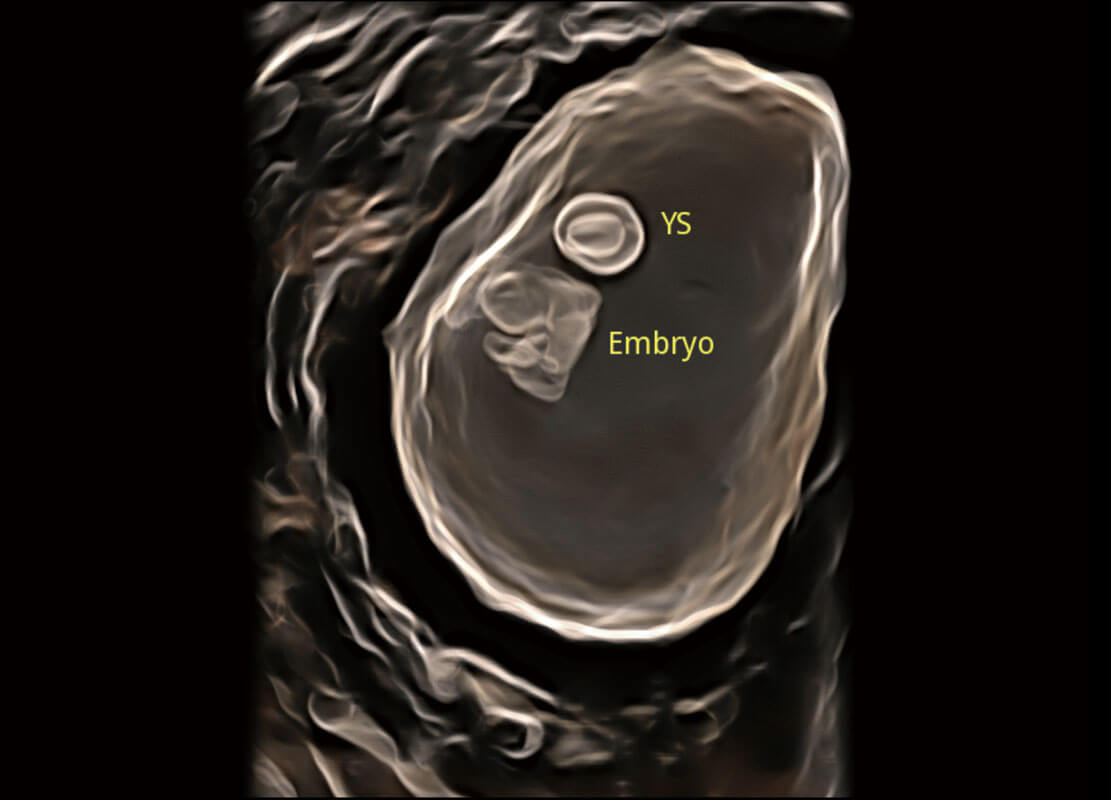

光影成像-孕囊

高分辨率容积成像-早孕胎儿

P60在胎儿早孕期超声筛查中为您带来优异的图像质量。